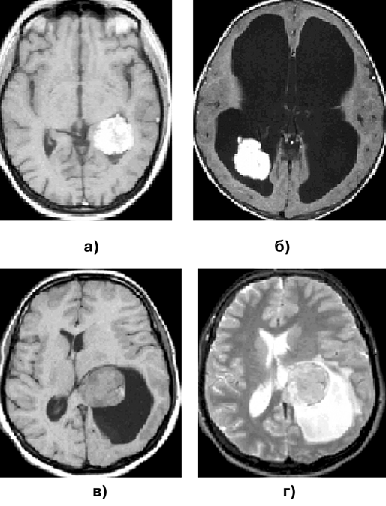

Если удаление опухоли сопряжено с риском нарастания неврологической симптоматики, может быть показано проведение только стереотаксической биопсии. При верификации глиомы низкой степени злокачественности возможно проведение курса дистанционной гамма-терапии без удаления опухоли (рис. 2а, б). В отдельных случаях оправдано динамическое наблюдение за больным (рис. 2в, г).

Рисунок 2. Фибриллярная астроцитома:

а — фибриллярная астроцитома левой лобно— височной области (КТ с контрастным усилением до лучевой терапии); б — фибриллярная астроцитома левой лобно-височной области (КТ с контрастным усилением через 5 лет после лучевой терапии); в — фибриллярная астроцитома левой лобно-височной области (МРТ, Т1-взвешенные изображения, до стереотаксической биопсии); г — фибриллярная астроцитома левой лобно-височной области (МРТ, Т1-взвешенные изображения, через 4 года после стереотаксической биопсии)